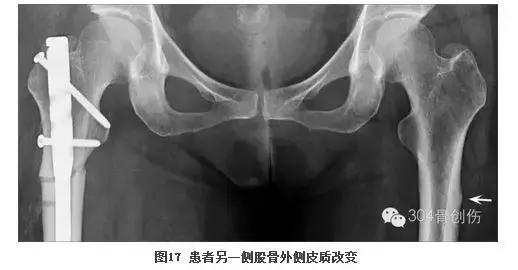

通过这个病例感悟颇深,使我想起了循证医学的主要创始人、国际著名临床流行病学家David Sackett(图15),他将循证医学定义为:“慎重、准确和明智地应用目前可获取的最佳研究证据,同时结合临床医师个人的专业技能和长期临床经验,考虑患者的价值观和意愿,完美地将三者结合在一起(图16),制定出具体的治疗方案”。现代循证医学要求临床医师既要努力寻找和获取最佳的研究证据,又要结合个人的专业知识包括疾病发生和演变的病理生理学理论以及个人的临床工作经验,结合他人(包括专家)的意见和研究结果;既要遵循医疗实践的规律和需要,又要根据“病人至上”的原则,尊重患者的个人意愿和实际可能性,尔后再作出诊断和治疗决策。此例粗隆下骨折如果仅凭经验处理,骨折顺利愈合,但仔细看看患者的另一侧股骨近端(图17),让人不寒而栗,能敢保证另一侧不发生骨折么?不经过这样一次有意义的讨论,哪能有这么多的收获?